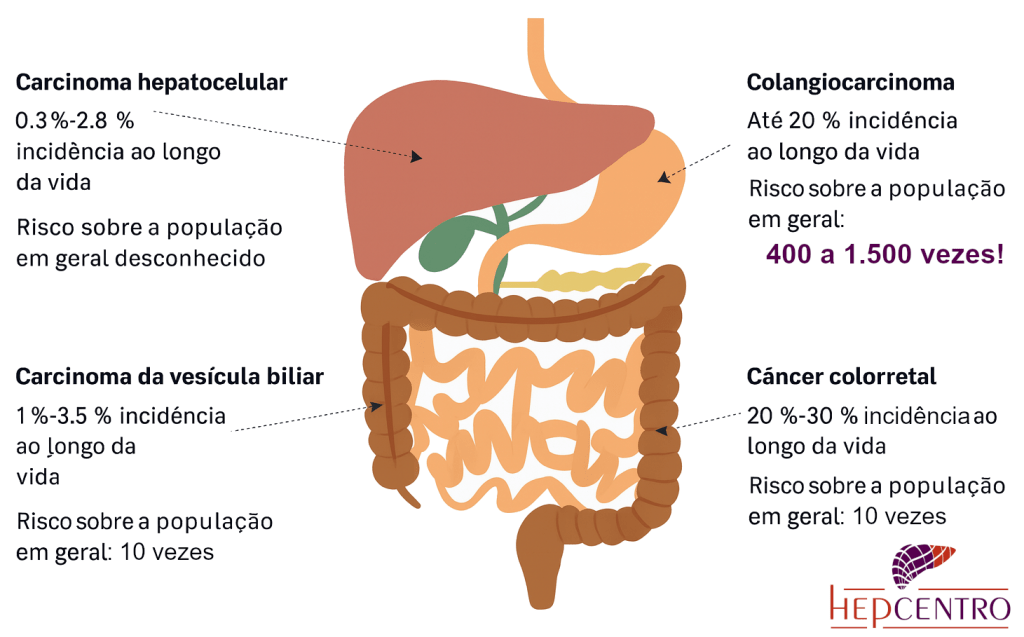

Um destaque muito importante em relação às complicações da CEP é o risco de desenvolvimento de câncer. O risco de câncer das vias biliares é muito aumentado, sendo responsável por 32% dos óbitos nos portadores da CEP. O risco de câncer do intestino é mais alto, particularmente quando a doença vem acompanhada de doença inflamatória intestinal, sendo responsável por 8% dos óbitos. Apenas 18% dos portradores acabam falecendo por insuficiência hepática, e 9% por complicações pós transplante. Por esse motivo, é fundamental realizar exames periódicos para rastreamento desses cânceres.